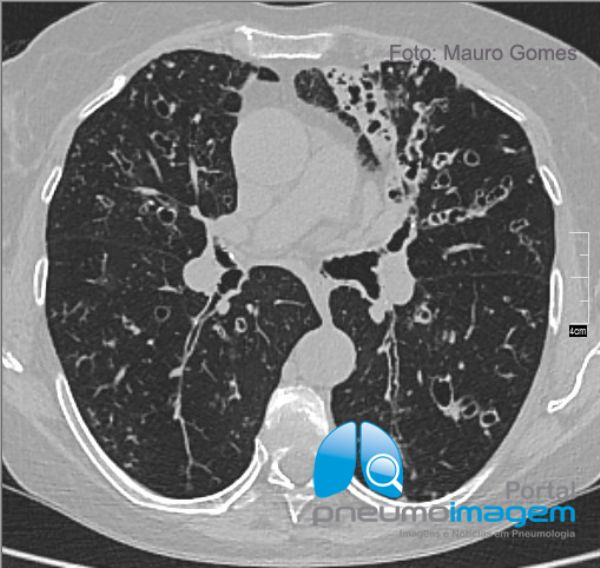

Neste corte tomográfico na região da carina é possível observar as bronquiectasias centrais e inúmeros nódulos centrolobulares que predominam no lobo médio e língula.

In this tomographic section in the carina region it is possible to observe the central bronchiectasis and numerous centrilobular nodules that predominate in the middle lobe and lingula.